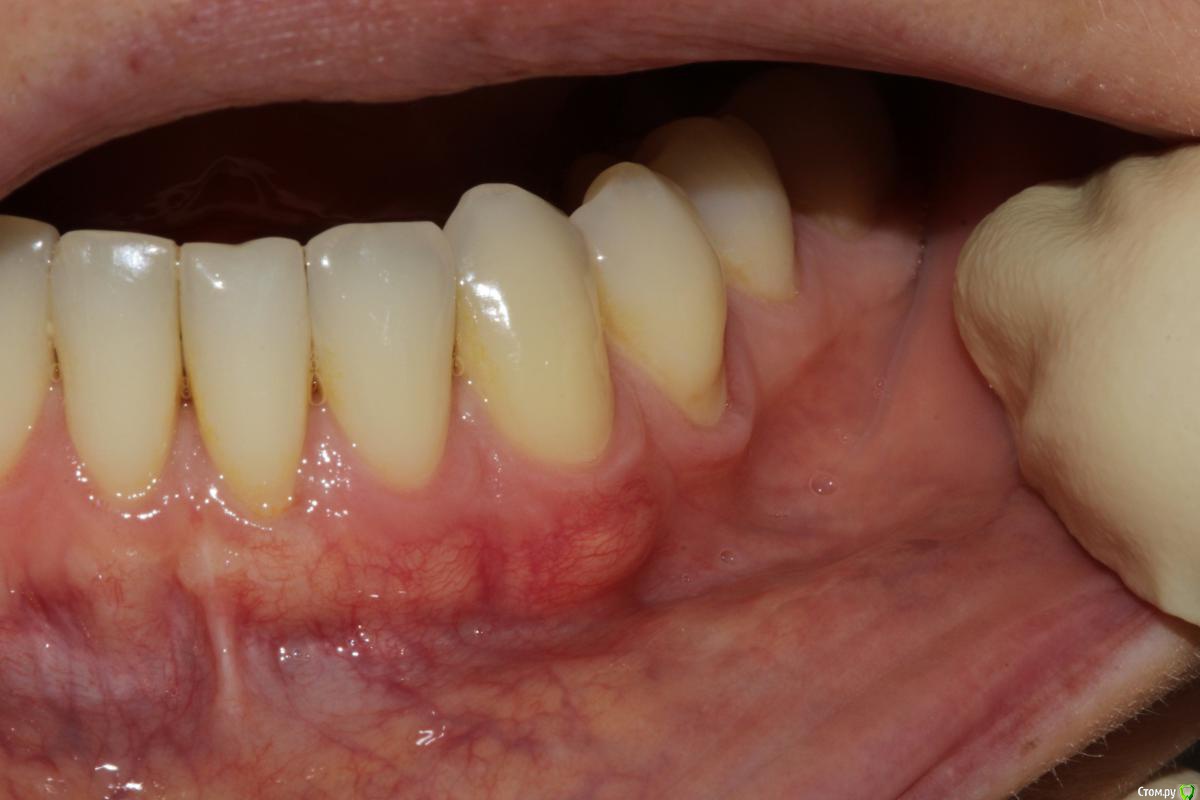

Dc.Petrov Опубликовано 18 сентября, 2015 Поделиться Опубликовано 18 сентября, 2015 Хочу узнать мнение коллег. Можно ли считать результат удовлетворительным? Рассчитывал на лучший итог. 15 Ссылка на комментарий

zzkz Опубликовано 19 сентября, 2015 Поделиться Опубликовано 19 сентября, 2015 через 3-6 мес можно точно сказать, на сегодня все нормуль. 31 еще можно подтянуть. Ссылка на комментарий

Dc.Petrov Опубликовано 21 сентября, 2015 Автор Поделиться Опубликовано 21 сентября, 2015 Почему четверку обошли стороной? Цель изначально была закрыть 31Сейчас уже жалею, что 34 не сделал Ссылка на комментарий

zzkz Опубликовано 22 сентября, 2015 Поделиться Опубликовано 22 сентября, 2015 До ЦЭС у 31 и 34 кажется что можно, по крайней мере по фото Ссылка на комментарий

Dc.Petrov Опубликовано 22 сентября, 2015 Автор Поделиться Опубликовано 22 сентября, 2015 с 34 понятно, с ним поработаю . Просто на одном том же месте (31) есть ли смысл повторять ? Ссылка на комментарий